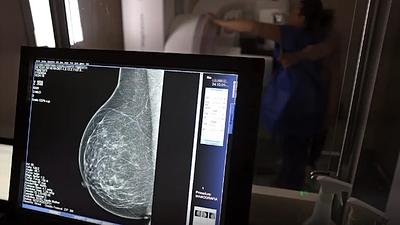

Especialistas reafirmam eficácia da mamografia para prevenir câncer de mama

Os vídeos que circulam na Internet chegam a associar a mamografia ao surgimento de câncer não apenas de mama, mas em outras partes do corpo e também como causa de inflamação e de transtornos de saúde.